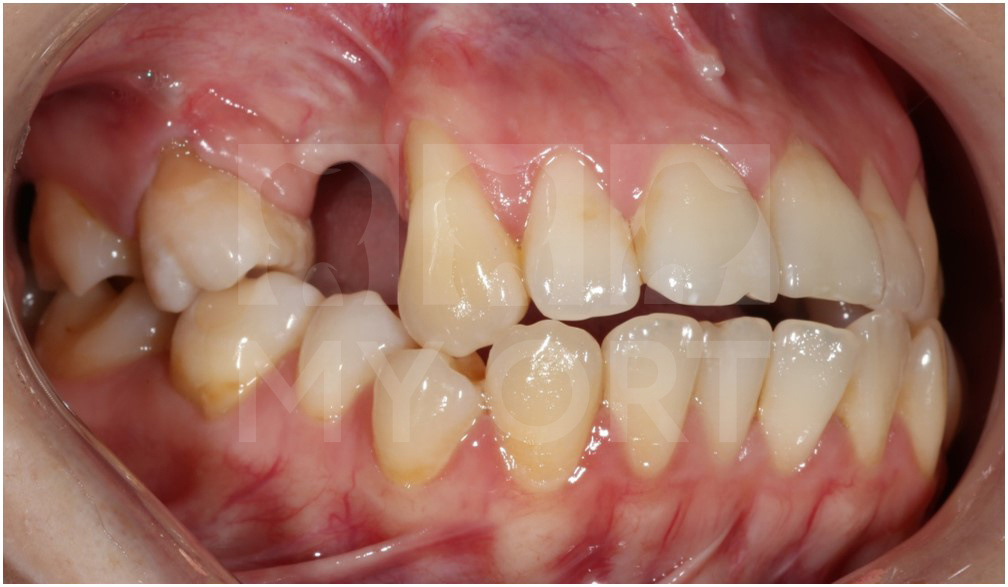

Всё лечение заняло 26 месяцев. Посмотрите какой результат у нас получился. Я и моя пациентка очень им довольны!

Результат после

Дальше пациентке нужна костная пластика, имплантация и протезирование 4 и 5 зубов у хирурга и стоматолога-ортопеда. Все условия, с точки зрения ортодонтии успешно исполнены.